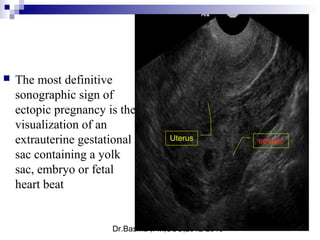

 The most definitive

sonographic sign of

ectopic pregnancy is the

visualization of an

extrauterine gestational

sac containing a yolk

sac, embryo or fetal

heart beat

ectopicUterus